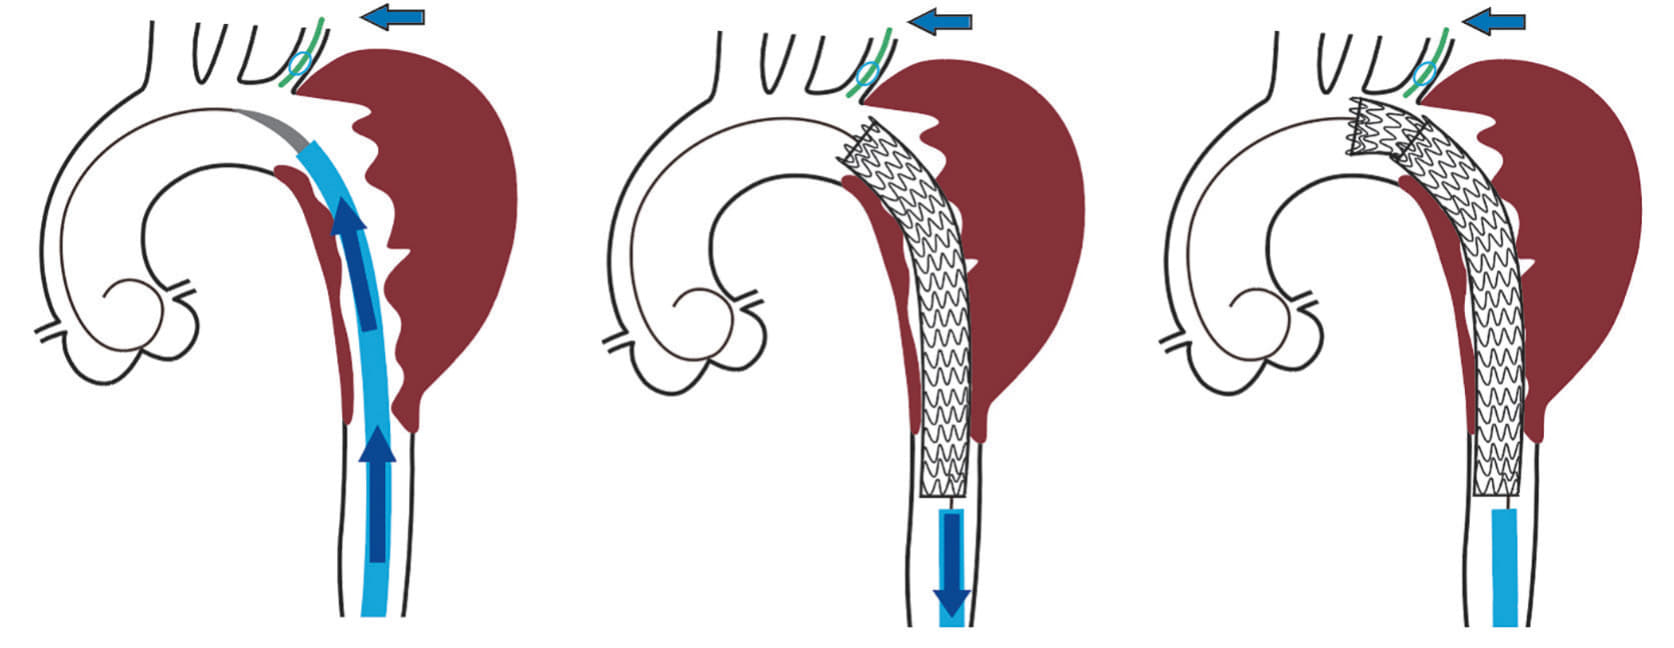

高度粥状硬化を伴う大動脈病変(shaggy aorta)に対して胸部大動脈ステントグラフト内挿術(TEVAR)を行う際は塞栓症をいかに避けるかが重要なポイントとなる。体外循環回路や血栓回収フィルターを用いた方法も報告されているが1,2、高度な技術を必要とする。当科では65 cm ゴア® ドライシール フレックス イントロデューサシースを用いて2本のゴア® TAG® コンフォーマブル 胸部大動脈ステントグラフト アクティブコントロールシステムを「Stepwise」に留置していく方法(Minimal manipulation approach:図1)を行うことで塞栓症の予防に努めており3、これを紹介する。

ドライシール フレックス イントロデューサシース内に1本目のTAG® コンフォーマブル ステントグラフト(TGM343410J)を挿入し、ドライシール フレックス イントロデューサシースをEVAR時のように抜退して(図 3b)、大動脈頂部(Zone 3近く)から末梢のランディングゾーンまでステントグラフトでカバーするように静かに展開する。シースとステントグラフトで「 鋪装 」された経路を通して中枢用の2本目のTAG® コンフォーマブル ステントグラフト(TGMR404015J)をZone 2まで先進させ、左鎖骨下動脈バルーンプロテクション下にゆっくり展開して、予定したデバイスを留置した(図5a, b)。

本症例で用いたアプローチでは表面が平滑なドライシール フレックス イントロデューサシースを治療予定部近くまで進めておき、粥状硬化の強い近位下行大動脈の大部分を「Windsock effect」が少ないと思われるTAG® コンフォーマブル ステントグラフトでカバーすることで壁在血栓とシース又はデバイスの摩擦を最小限とすることが狙いである。エビデンスはないが、TAG® コンフォーマブル ステントグラフトの独特の展開様式(末梢側から展開するので粗大な塞栓子は末梢に飛散しない)も塞栓症予防には有利になると考えている。